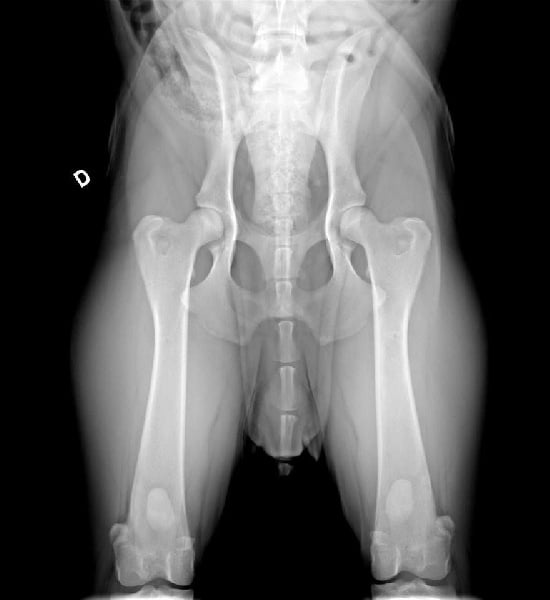

Radiographie des hanches (Dr Haudiquet)

Casanova est un jeune chien bien construit, avec une ossature correct, une tête typique et avec un potentiel génétique très intéressant. Radiographié HD A/B par le spécialiste Dr Haudiquet.

DSRA : N/N Clear Dysplasie des hanches : A/B |